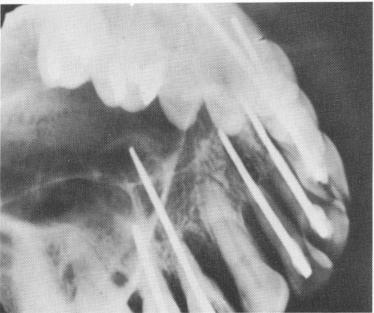

Fig. 13-62. Overshooting accidents. A, The post overshot a lower premolar and went through the jaw. It was immediately withdrawn into the bone and this radiograph taken. B, Five weeks later. C, In this case, overshooting was detected only after cementation. Radiograph taken 1 year after the operation. (From Orlay, H. G.: Endodontic implants, J. Oral Implant Transplant Surg., pp. 44-53, 1965.)

Fig. 13-63. Pins perforating the maxillary sinus. Although usually no problems arise for the patient, the pins become more unstable. (Courtesy H. G. Orlay.)

Fig. 13-64. Pins perforating the nasal vestibulum as well as the sinus. The pin in the nose will be very irritating. (Courtesy H. G. Orlay.)